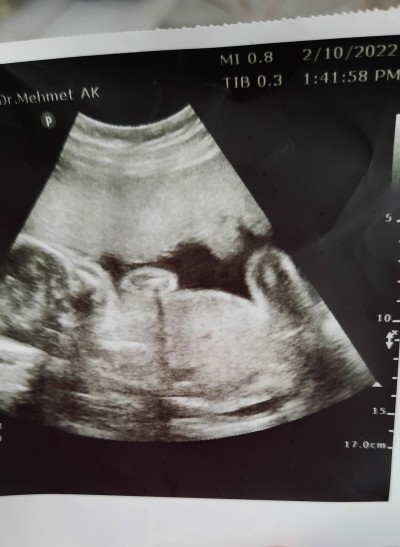

23 haftalik cinsiyet tahmini anlayanlar bakabilir mi rica etsem

Pamuk bir prenses bu bence:)

Gizliyor ama kiz gibi dedi:)

kiz bu yaaa

Ayy kız buuuuu